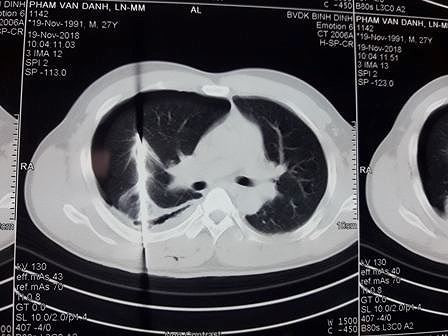

Kết quả chụp phim của bệnh nhân. Ảnh: Bệnh viện cung cấp

Sau khi tiếp nhận bệnh nhân, các bác sĩ đã tiến hành đặt ống dẫn lưu màng phổi để cấp cứu cho bệnh nhân Đ. Khi đưa bệnh nhân đi chụp phim, kết quả xác định lưỡi dao nằm trọn trong lồng ngực và đâm vào phổi.